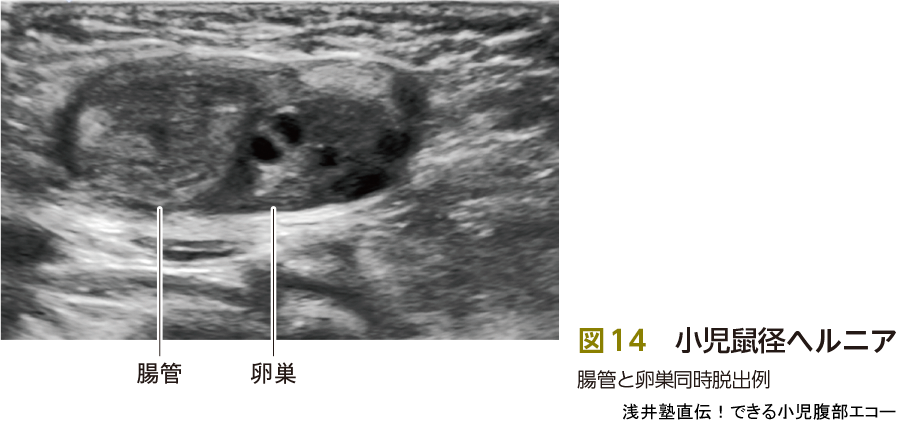

2)嵌頓ヘルニア

脱出がない場合は診断が困難です.そこで,立位,ジャンプ,バルーンを膨らませるなどいろいろな手法を用いて腹圧をかけての走査を試みます(図13).また,内容物の確認も重要です.卵巣脱出例は無理な圧迫は禁忌です(図14).捻転の合併,ほかの奇形を伴う可能性4)もあるため,卵巣の脱出がみられたら,捻転はないかを血流信号,Bモードでの連続性を確認し評価する,ほかの奇形がないかもエコーで確認する必要があります.